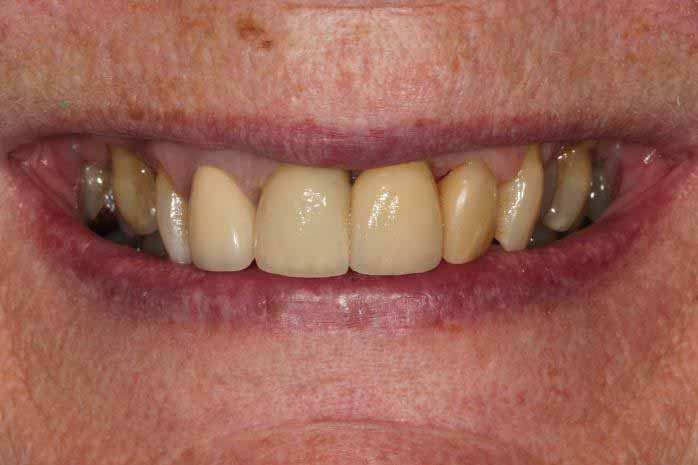

Upper Front Tooth Implant

Both upper front teeth were in a bad way, the upper left one had to be removed as was beyond repair, this was replaced with an implant and a temporary crown on the same day; the upper right front tooth was repaired with a crown. Photos show the result with the definitive crowns after 3 months of treatment.